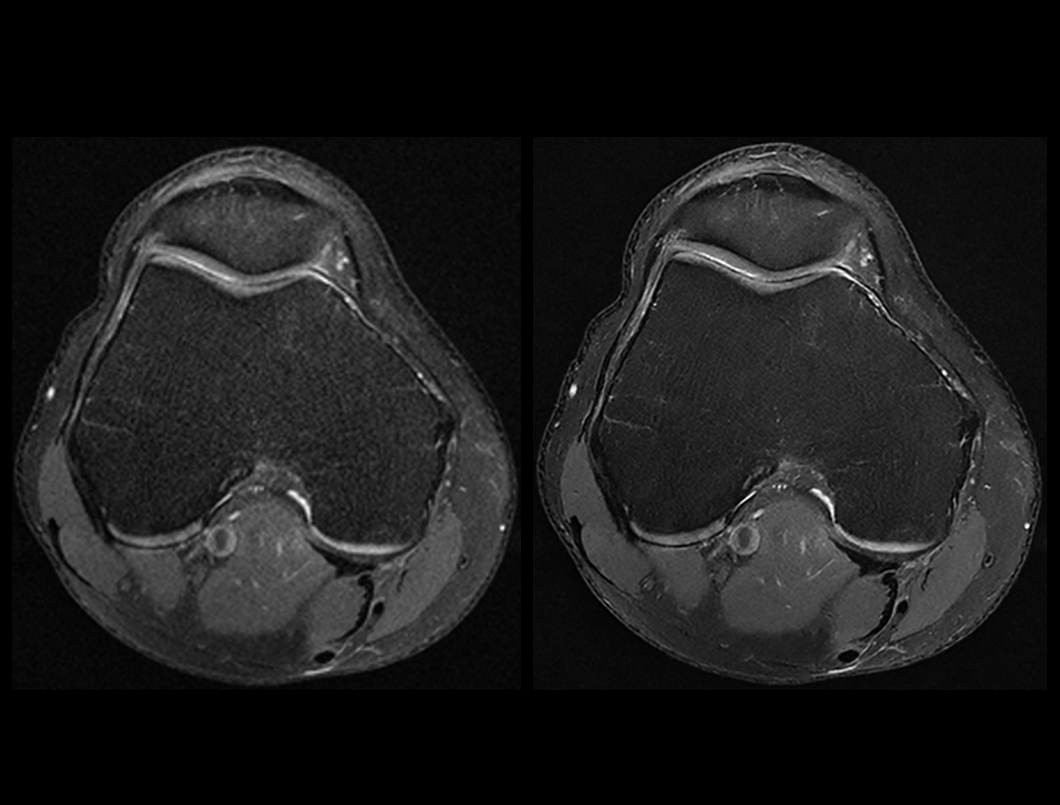

膝关节 PDW FS

常规成像 (2:32 min) vs. uAIFI DeepRecon™ (2:32 min)

0.35×0.35×3 mm3